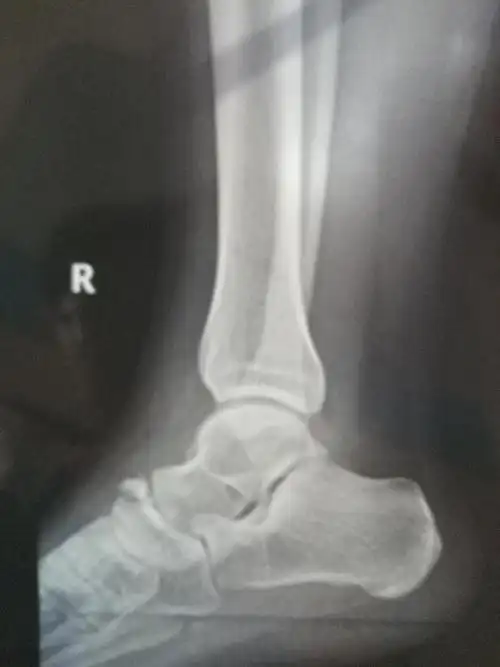

右足舟骨撕脱性骨折